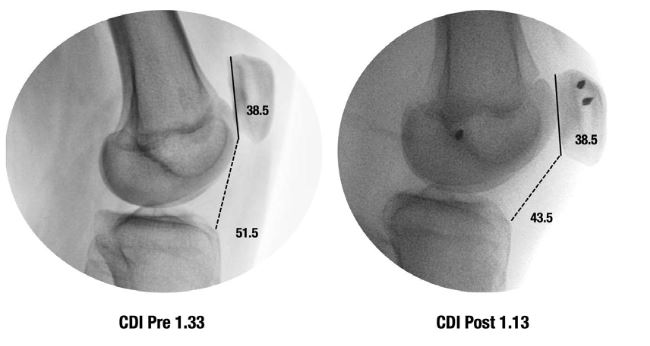

Respecto a los resultados secundarios, el 92 % de los pacientes que practicaba deporte antes de la cirugía retomó la actividad. Según nuestra clasificación, el 85 % lo hizo al mismo deporte y al mismo nivel (Grado 1), mientras que el 8 % cesó toda actividad deportiva por desinterés o falta de tiempo (Grado 4). La longitud rotuliana no mostró cambios significativos luego de la cirugía, con valores medios de 30.45 ± 3.42 mm en el preoperatorio y 29.63 ± 3.93 mm en el postoperatorio (p = 0.11). En cambio, la distancia entre la faceta articular de la rótula y la esquina anterior de la epífisis tibial superior disminuyó significativamente, de 42.92 ± 7.75 mm a 35.72 ± 6.00 mm (p <0.0001). Asimismo, el ICD se redujo de forma significativa, de 1.41 ± 0.10 a 1.18 ± 0.10 (p = 0,0001) (Fig. 1), con una disminución promedio de 0.23 en los controles radiográficos realizados a los 6, 12 y 24 meses. Ningún paciente presentó complicaciones postoperatorias (Tabla 2).

Figura 1. Paciente femenina de 13 años incluida en la serie, con diagnóstico de inestabilidad patelofemoral recurrente. Radiografías de perfil muestran la disminución del índice de Caton-Deschamps (ICD) luego de la reconstrucción del ligamento patelofemoral medial. La imagen pertenece a un caso real del estudio y se publica con el consentimiento informado de los padres/tutores.